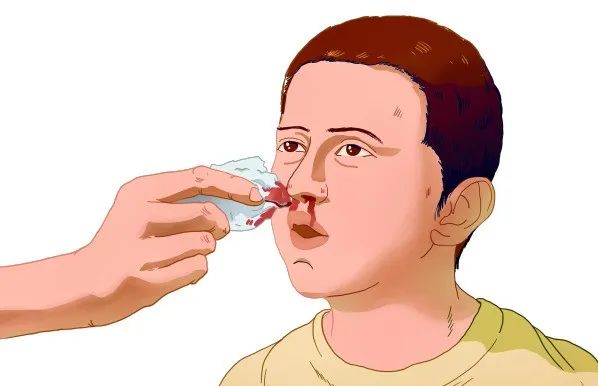

湖南益安生物 | 鼻腔专用止血海绵,国产高端止血材料

时间:2024-12-09在医疗科技日新月异的今天,湖南益安生物科技有限公司以其卓越的研发能力和创新精神,为医疗行业带来了诸多创新产品。其中,鼻腔止血海绵作为该公司的一款明星产品,以其高效止血、促进愈合、使用便捷等显著优势,赢得了广大患者和医护人员的青睐。 湖南益安生物科技有限公司…查看全文